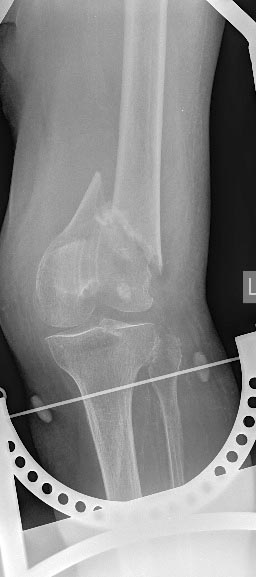

Контрольные рентгенограммы

Не совсем понятно расположение винтов в опорной пластине, а именно 2 кортикальных винтов, находящихся практически в зоне перелома. С уважением.